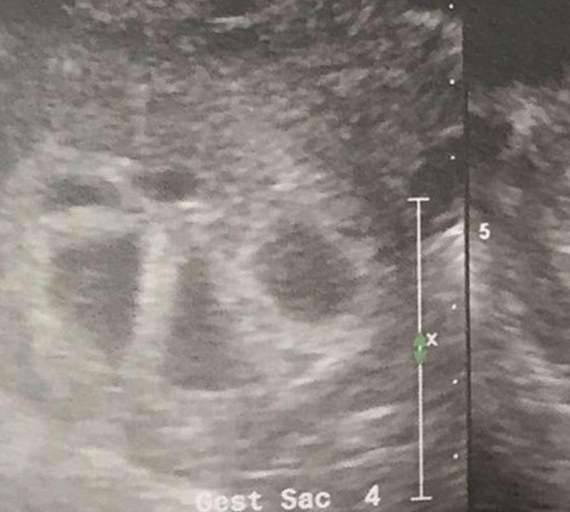

▼塔奇已经有了2个女儿,去年时她与丈夫想要最后一个孩子,并希望最好是个男孩。成功怀孕后,他们到医院做检查,医生告诉他们塔奇怀了双胞胎。之后他们又用另一台超音波机器观察胎儿,医生却发现了5个心跳,原来她孕育的是五胞胎。这个好消息让她与丈夫兴奋不已。